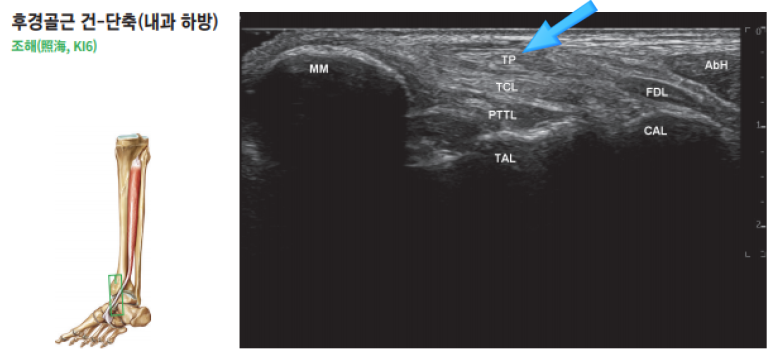

한의학에 "조해혈(照海穴)"이라는아주 중요한 혈자리가 있습니다.

안쪽 복숭아뼈 바로 아래 움푹 들어간 곳인데요.

이 곳은 족소음신경 경락이 지나가는 길목이며,

놀랍게도 해부학적으로 이 조해혈 바로 아래로

후경골근건이 지나갑니다.

경혈초음파 "조해혈"

이 "조해혈" 주변에 초음파 프로브를 대고

경혈의 표준 초음파 영상과 비교하며,

문제를 확인합니다.

특히 해당 혈자리 주변은 후경골근건 외에도

복잡한 구조물이 많기 때문에

통증의 원인이 정말 후경골근건이 맞는지

감별하는 것이 매우 중요합니다.

정확한 진단으로

병변부위를 세밀하게 찾아냈다면,

이제 치료는 훨씬 정밀해집니다.

초음파 화면으로 실시간으로 보면서,

염증을 줄이고 조직 재생을 돕는

PDRN 연아약침을

문제 부위에 정확하게 주입하는 겁니다.

위험한 구조물을 피하면서

아픈 힘줄, 손상된 인대, 염증이 생긴 관절낭에

딱 맞춰서 시술하는 거죠.